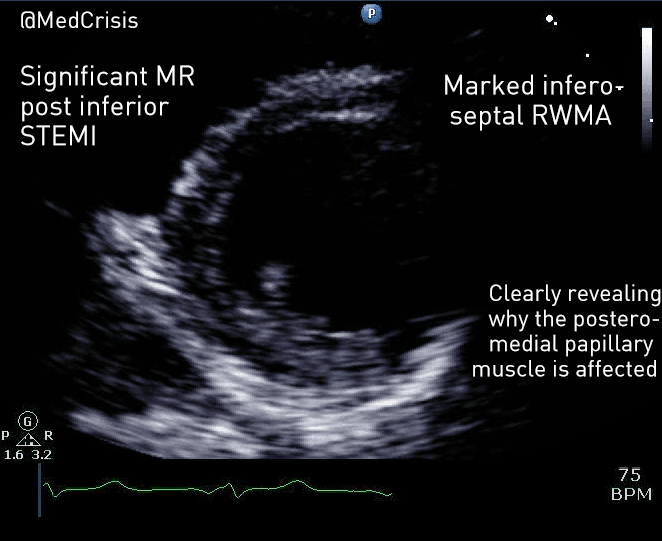

This parasternal short axis view gives the clearest demonstration of the problem. A regional wall motion abnormality is clearly seen affected the infero-septum and inferior wall. The rest of the left ventricle is contracting well.

Therefore one can appreciate why mitral valve problems are more common following an inferior STEMI. In this case an almost akinetic segment, which included the posteromedial papillary muscle, caused the posterior mitral valve leaflet to become fixed, causing mitral regurgitation. Even though overall left ventricular function was only mildly impaired on the echocardiogram, the regurgitant pressure into the lungs can precipitate pulmonary oedema.